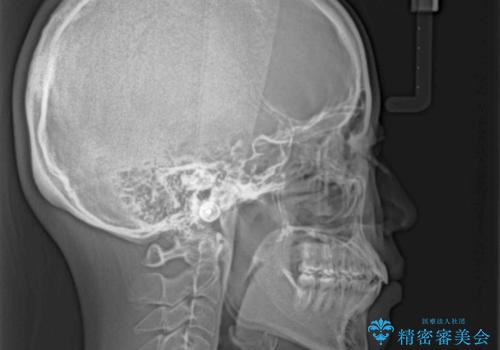

舌の突出癖の影響か、なかなかスペースが閉じきらず、治療期間は予定よりも長期間となりました。

舌突出癖改善のトレーニングの重要性を認識することとなりました。